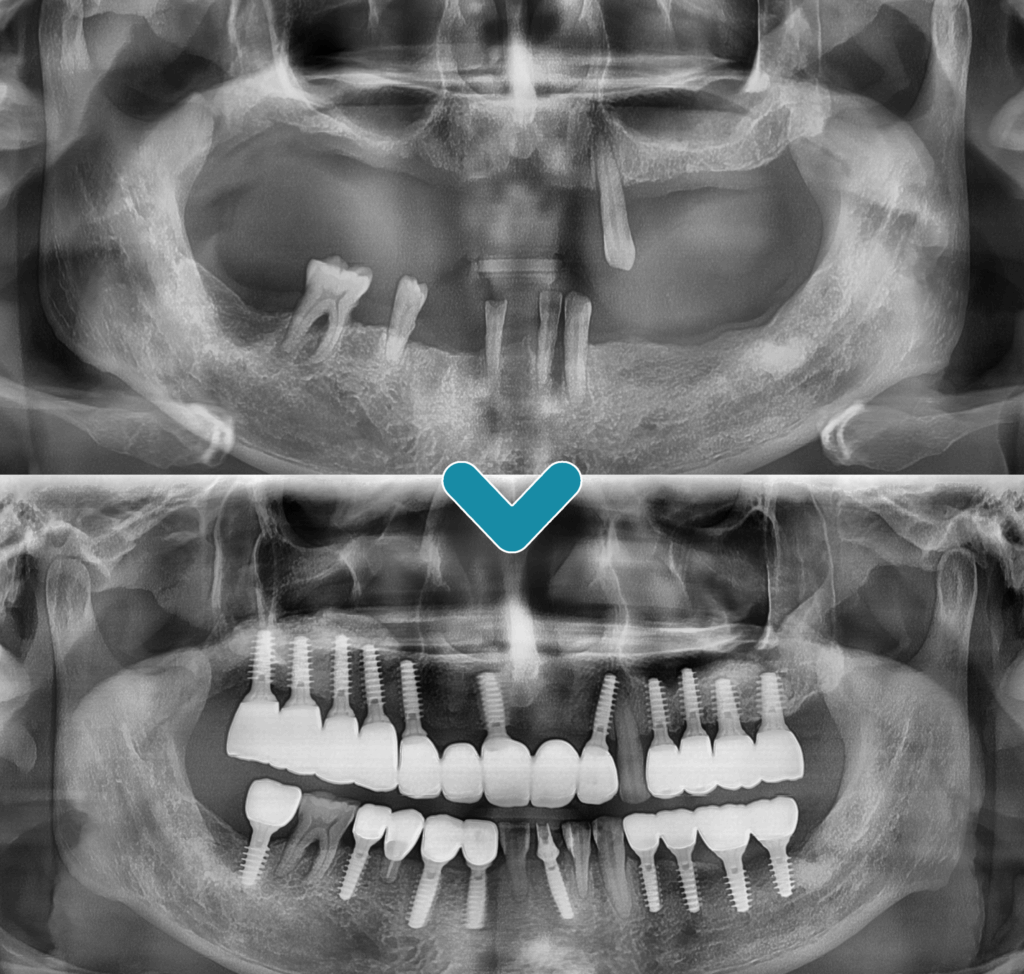

오늘은 구강 내 전체적으로

남아 있는 예후가 좋지 않은

치아들을 발치한 후

전주신시가지치과 전체임플란트를 진행하신

환.자분을 소개해 드리려고 합니다.

환자분은 기존에 틀니를 제작하여

사용하셨지만 점차적으로 남아 있는

자연치들이 흔들리고 상태가 좋지 않아져

치료 상담을 위해 내원해 주셨습니다.

잇몸뼈가 많이 흡수되어

많은 양의 뼈이식을 동반하여

최소침습 임플란트 식립을

진행하기로 하였습니다.

치료를 마무리한 후의 모습입니다.